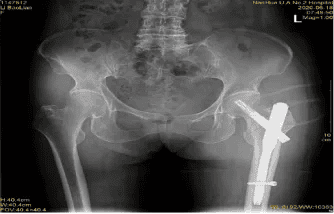

三、需要进行哪些辅助检查?

X片: CT: